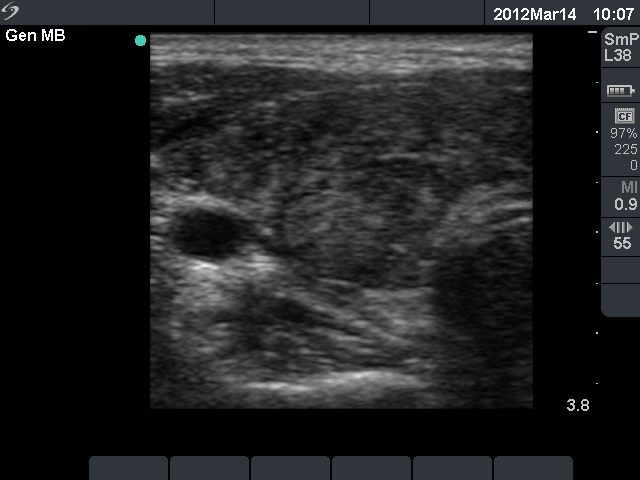

Six months after initial investigation (second row):

Clinical presentation: she had no complaints till the last several week, then she noticed increase in heart rate and fatigue.

Palpation: both thyroids were enlarged.

Functional state: hyperthyroidism with TSH-level 0.09 mIU/L, FT4 28.2 pM/L, FT3 12.8 pM/L.

Ultrasonography: the thyroids were hypoechogenic and presented increased vascularization.

Clinical diagnosis: recurrent hyperthyroidism caused by Graves's disease. We administered daily 20 mg methimazole. 2 months later when FT4 level has normalized the patient underwent radioiodine therapy.